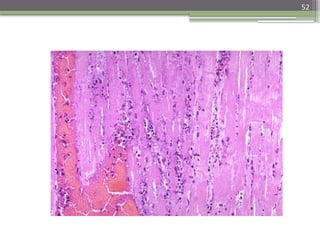

3-7 days

Gross - Hyperemic border with central- yellow tan

softening.

Microscope

- Macrophage and mononuclear infiltration as well as

fibrovascular response begin.

52

• Micrograph of infarcted myocardium undergoing

early organization with granulation tissue, and early

fibroblastic proliferation, the necrotic myocardium

here shows the typical hyper-eosinophilia, loss of

cross striations and absence of nuclei that is

associated with coagulative necrosis.

Micrograph of infarcted myocardium undergoing early organization

with granulation tissue, and early fibroblastic proliferation, the

necrotic myocardium here shows the typical hyper-eosinophilia, loss

of cross striations and absence of nuclei that is associated with

coagulative necrosis.